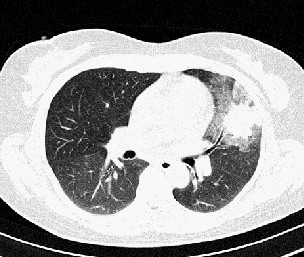

以下是引用汪涛同志在2007-5-15 21:54:00的发言:[br]左肺舌叶病变,周围渗出明显,病灶面积肺窗和纵隔窗有较大反差,同一叶前后病灶可见类似影像改变,后一病灶可见“直边征”考虑为渗出感染性病变,建议严格抗炎治疗后短期复查。